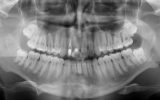

One of the standout contributions of the seminar was the clinical poster presented by Nino Kneževič, featuring a patient treated at Center Hočevar.

The poster provided a clear and structured overview of the pre-, intra-, and postoperative stages of ceramic implant placement, illustrating:

the biological reasoning behind treatment decisions,

the dynamics of soft- and hard-tissue healing,

and the long-term functional and aesthetic outcomes achievable with ceramic implants.